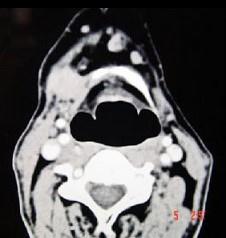

问题 男,45岁,右侧颌下扪及一包块约4个月,无痛,PE:包块质硬,表面欠光整,移动度较差,CT如图所示,最可能诊断是()

选项 A.颌下腺神经源性肿瘤 B.颌下腺腺瘤 C.颌下腺淋巴瘤 D.颌下腺腺癌 E.颌下腺转移瘤

答案 D